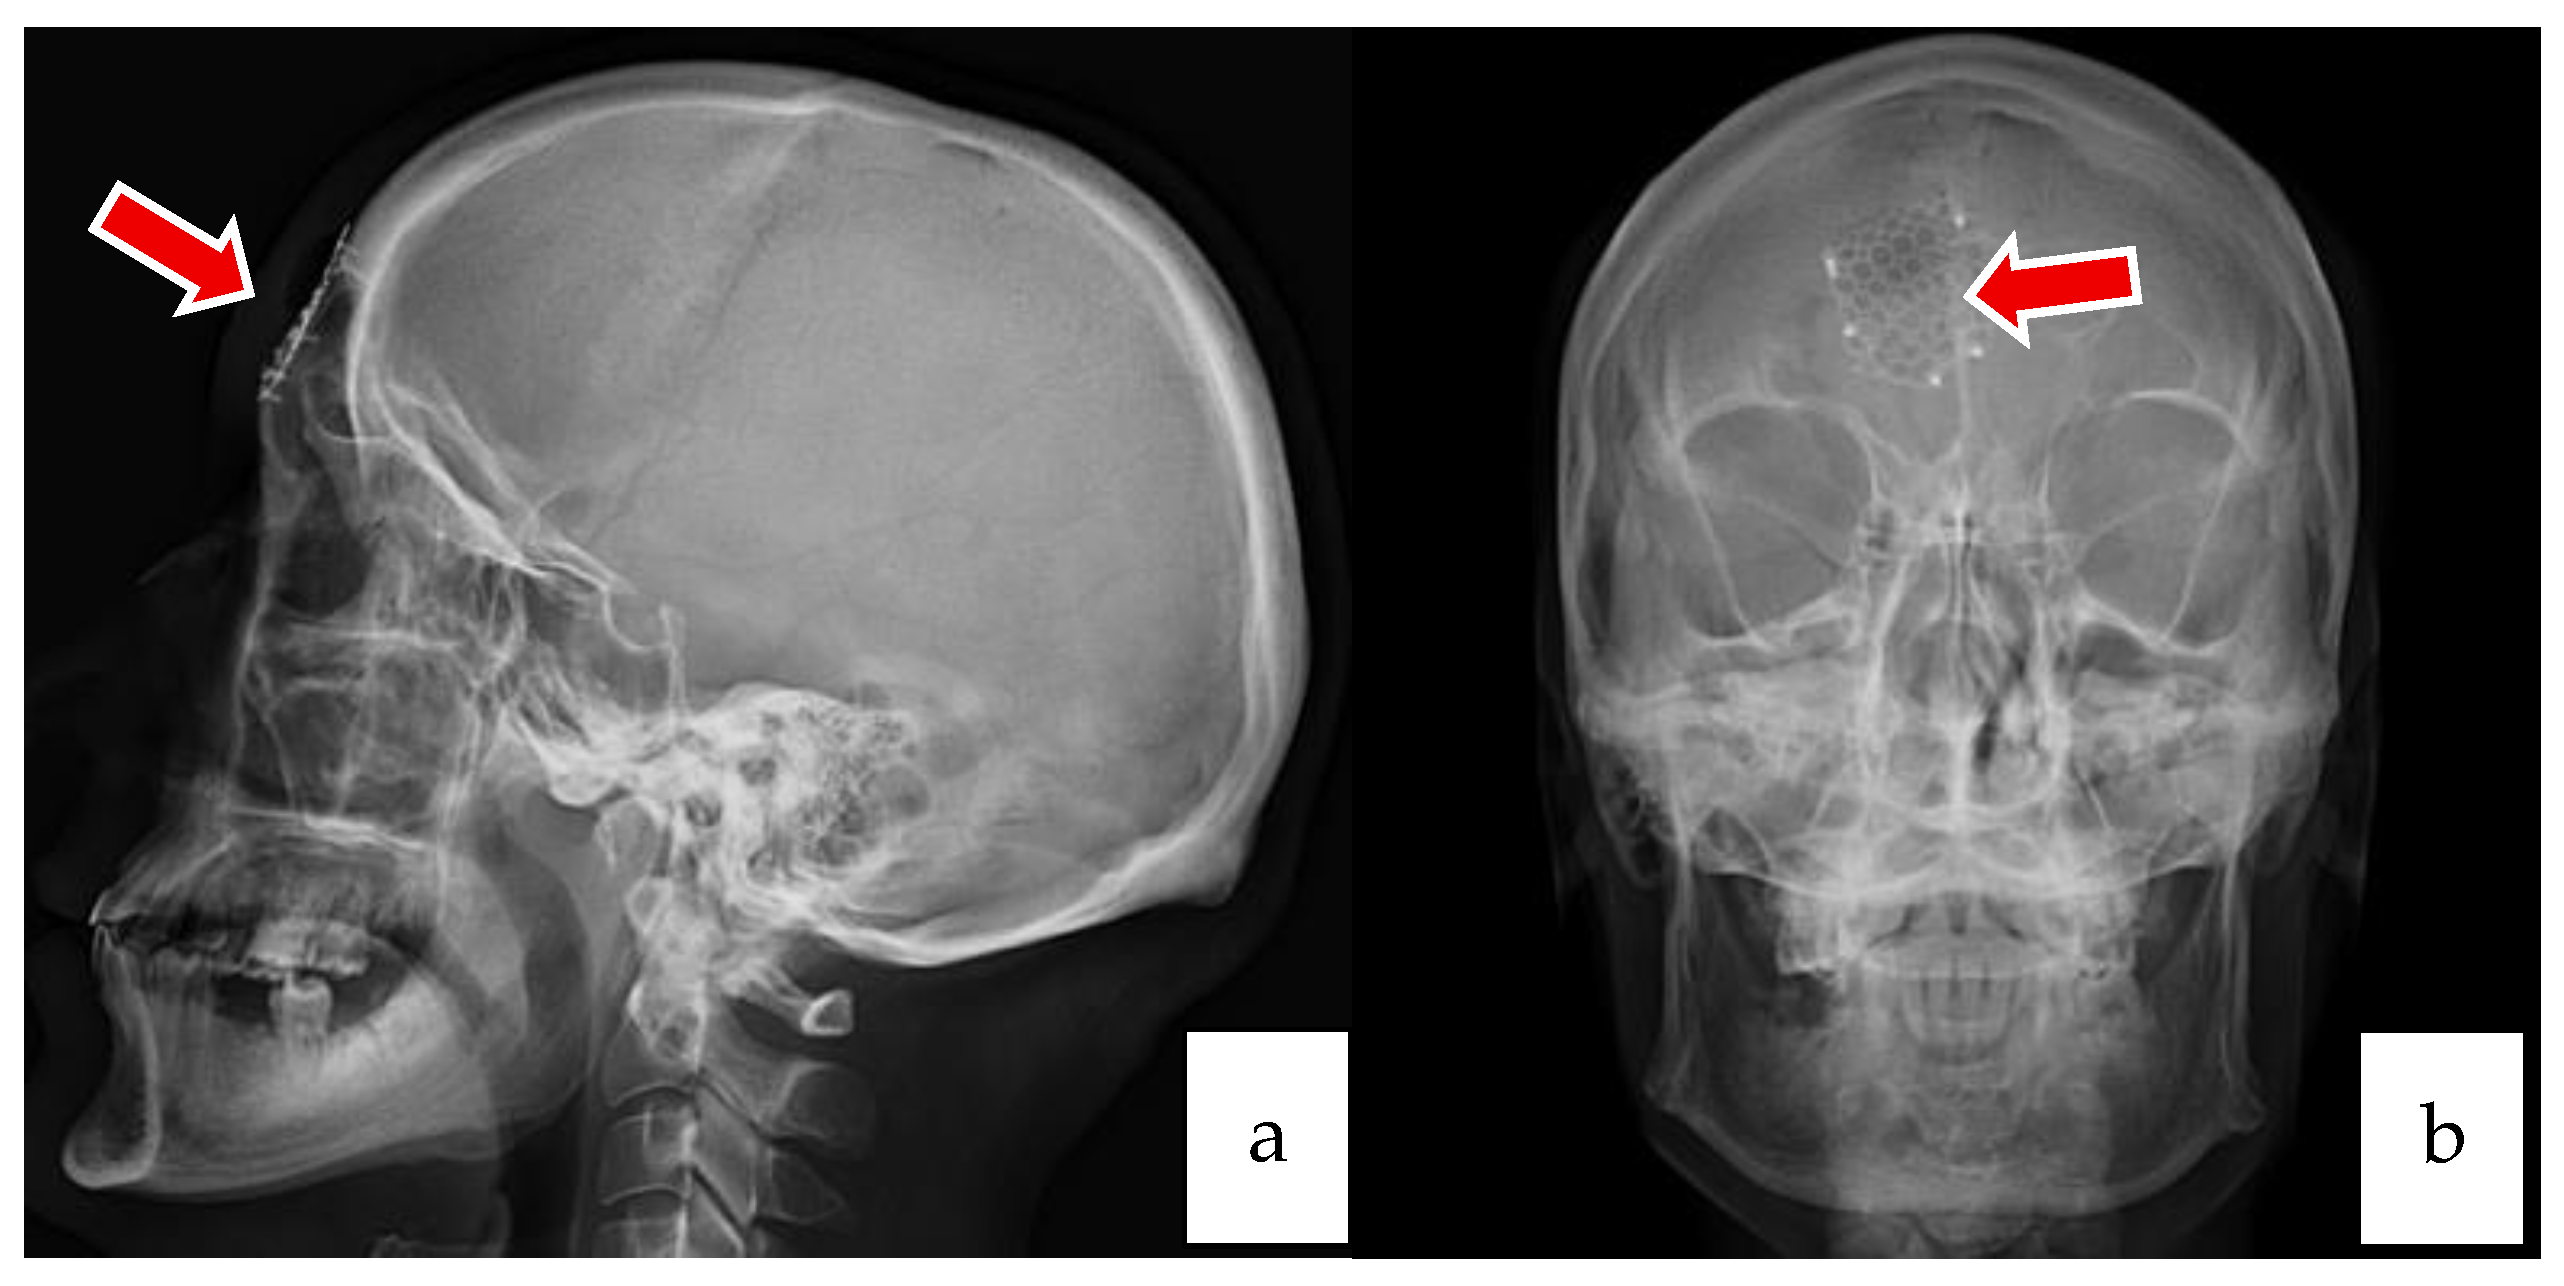

2.2. Case 2